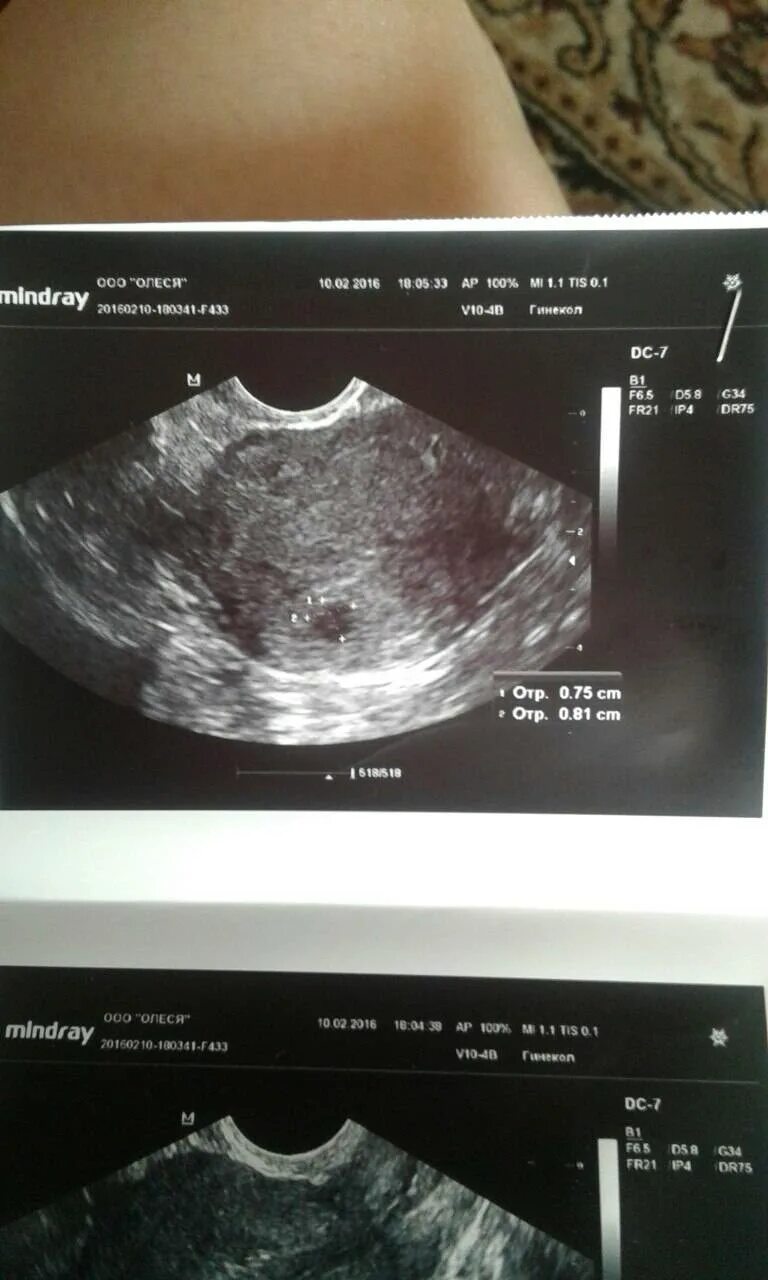

Как называется узи на ранних сроках